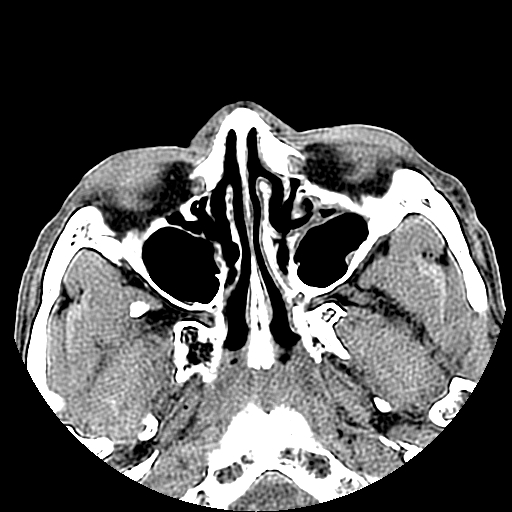

以下是引用liaoqiang在2008-7-16 21:15:00的发言:[br]右侧鼻骨骨折

以下是引用zxd95在2008-7-16 21:39:00的发言:[br]右侧上颌骨额突骨折。[br][br][br][br]